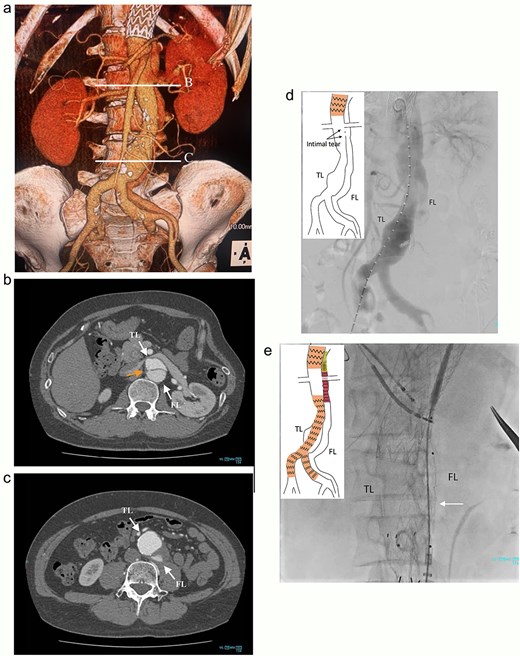

At 2-year post-procedure, CT follow-up showed AAA expansion to 56 mm, and FL dilation to 25 mm. The contrasted CT showed small inflow to the FL from the TL through the gap between the intimal flap and the FL stent graft via a residual intimal tear, as well as reversal flow from re-entry at the EIA (Fig. 2a–c). A second-stage endovascular repair was planned for completing the TAAA repair. Under local anesthesia, the gap between the FL stent graft and the intimal flap was occluded using DELTAFIL (Jonson & Jonson, NJ, USA) from FL side to close a residual intimal tear (Fig. 2d). The eighth intercostal artery and the third lumbar artery were occluded using DELTAFIL and GARAXY G3 (Jonson & Jonson, NJ, USA), respectively to block the backflow from these side branches. Then the 8 × 59 mm VBX (WL Gore & Associates, Newark, DE, USA) was deployed at left EIA covering the re-entry tear, successfully completing FL closure (Fig. 2e). The postoperative course was uneventful, with no paraplegia, and he was discharged on the postoperative day 4. The postoperative contrast-enhanced CT showed no contrast inflow into the FL. The CT imaging 3 years after the procedure showed the reduced diameter of abdominal aorta of 35 mm (Fig. 3a–c).

The contrasted CT 3D reconstruction 2 years after the false lumen (FL) stent graft placement (a; white arrow); the contrast-enhanced CT axial images showing small inflow to the FL from the true lumen through the gap between the intimal tear and the FL stent graft (b; arrow), and abdominal aortic aneurysm expansion to 56 mm (c; white arrow); the intraoperative angiography showing coiling of the gap between the intimal tear and FL stent graft (d; white arrow), and the VBX was deployed at left external iliac artery covering the re-entry tear (e; white arrow). TL: true lumen; FL: false lumen; SMA: superior mesenteric artery.